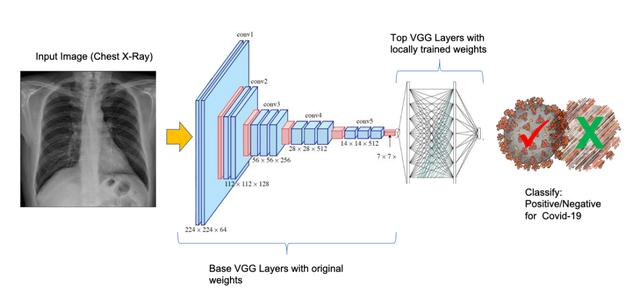

对抗Covid-19的一个重大挑战是检测病毒在人体内的存在,因此本项目的目标是使用扫描的胸部X光图像自动检测肺炎患者(甚至无症状或非病人)中Covid-19的病毒。这些图像经过预处理,用于卷积神经网络(CNN)模型的训练。

CNN类型的网络通常需要一个广泛的数据集才能正常工作,但是,在这个项目中,应用了一种称为“迁移学习”的技术,在数据集很小的情况下非常有用(例如Covid-19中患者的图像)。

该模型的训练是使用预定义的图像进行的,应用了称为“迁移学习”的技术。

迁移学习是一种机器学习方法,其中为一个任务开发的模型被重用为第二个任务中模型的起点。

Keras应用程序是Keras的深度学习库模块,它为几种流行的架构(如VGG16、ResNet50v2、ResNet101v2、Xception、MobileNet等)提供模型定义和预训练的权重。

使用的预训练模型是VGG16,由牛津大学视觉图形组(VGG)开发,并在论文“Very Deep Convolutional Networks for Large-Scale Image Recognition”中描述。除了在开发公共的图像分类模型时非常流行外,这也是Adrian博士在其教程中建议的模型。

重要的是要记住一个预训练过的CNN模型,如VGG16,被训练了成千上万的图像来分类普通图像(如狗、猫、汽车和人),我们现在需要做的是根据我们的需要定制它(分类X光图像)。理论上,模型的第一层简化了图像的部分,识别出其中的形状,这些初始信息非常通用(如直线、圆和正方形),因此我们不用再训练它们,我们只想训练网络的最后一层。